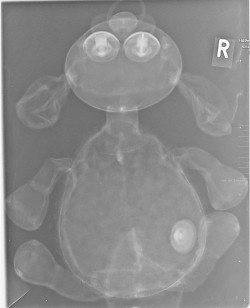

Erst das Kuscheltier - dann das Kind

Kinder kommen oft sehr ängstlich mit Kuscheltieren oder Puppen zum Röntgen. Um den Kindern diese Angst zu nehmen, kann man vor deren neugierigen Augen, zuerst die kuscheligen Begleiter unter die Röhre legen.

Spätestens wenn die Kinder die Bilder Ihrer Kuscheltiere sehen ist die Angst vorm Röntgen meist vergessen. So wie bei den unten abgebildeten Bildern.